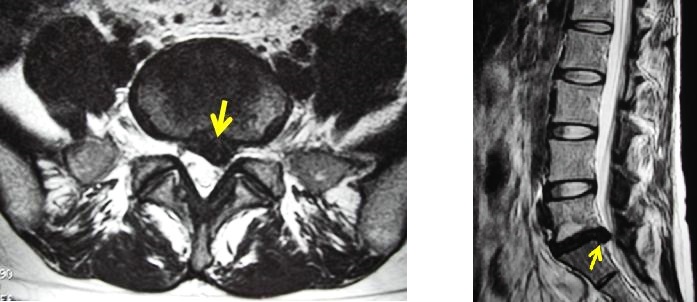

최근에는 허리디스크를 직접 그려낼 수 있는 MRI(핵자기공명영상) 검사가 많은 병원이나 진료소에서 외래에서 실시할 수 있게 되었기 때문에 진단에 소요되는 시간은 단축되고 진단의 정확도도 이전에 비해 현격히 높아지고 있습니다.

그러나 한편으로는 증상과 관계없는 디스크(이를 무증상 디스크라고 합니다)도 함께 검출되기 때문에 환자들이 불안감을 느끼는 경우도 있습니다.

무증상 디스크는 치료할 필요 없이 방치해도 좋으니 의사의 설명을 충분히 들어주세요.